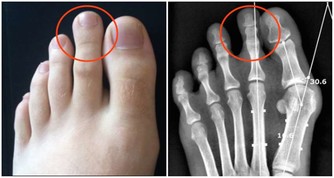

2、健康隱患。生病也是會導致噩夢的,如果長時間做同一個噩夢,夢到我們身體的某個部位,那可以預示著這個部位可能有問題,自己要多去注意。